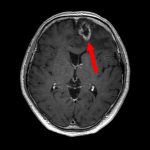

断層撮影

手術前1

手術前2